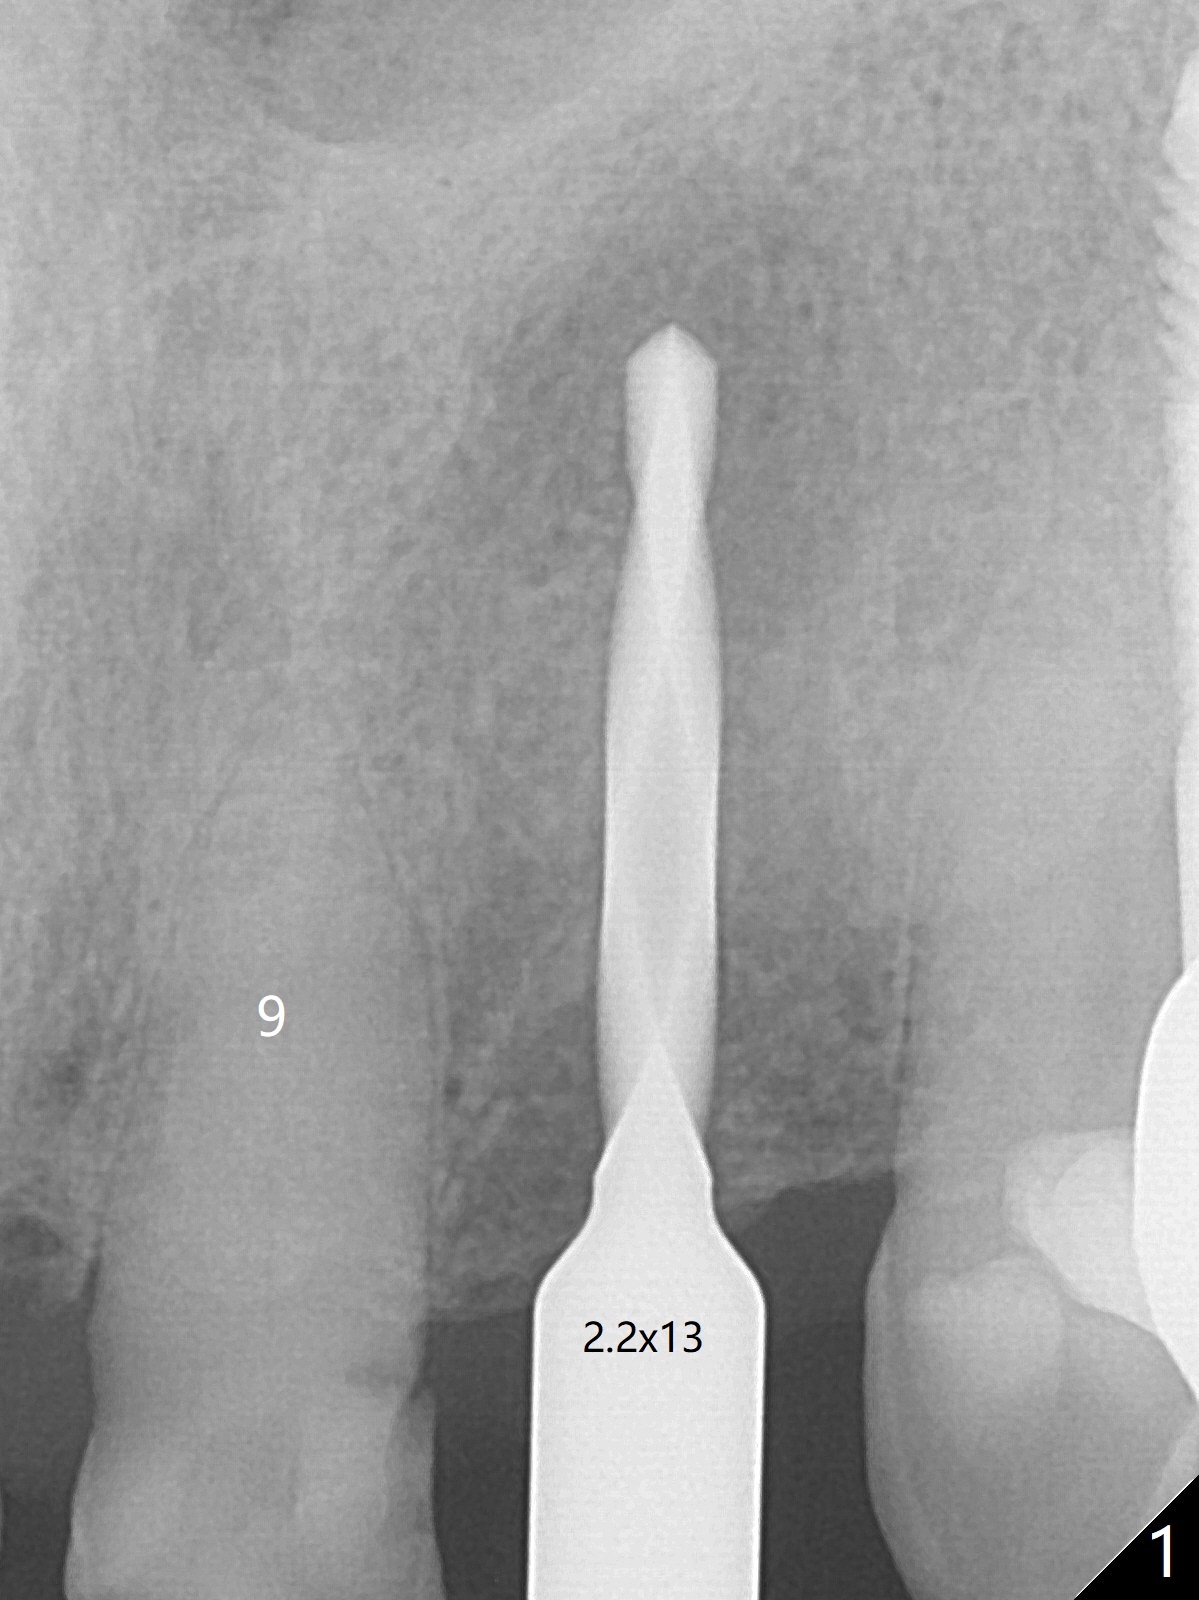

After undersized drilling in depth at #10 (2.2x13 mm (10.5 mm offset), Fig.1), a 2.5x13 mm 1-piece implant is placed (Fig.2,3), as compared to the design (Fig.3'). Following 3 more turns of the implant (~ 20 Ncm), bone graft and heavy buccal reduction of the coronal end of the abutment, an immediate provisional is bonded to the tooth #9 (Fig.4) and splinted to the tooth #11 with a twisted wire (Fig.5). To increase stability and reduce reduction, a 3 mm 1-piece implant could be used with 15 degree abutment. The implant remains stable 5 months postop (Fig.6). The implant seems to be flexible before heavy occlusal reduction; note the periimplant micro-space (Fig.7). The patient is a bruxer. The implant crown seems to be minimally mobile 2 months post cementation (Fig.8, without treatment). 牙冠粘固后1年1个月软硬组织正常(图九)。